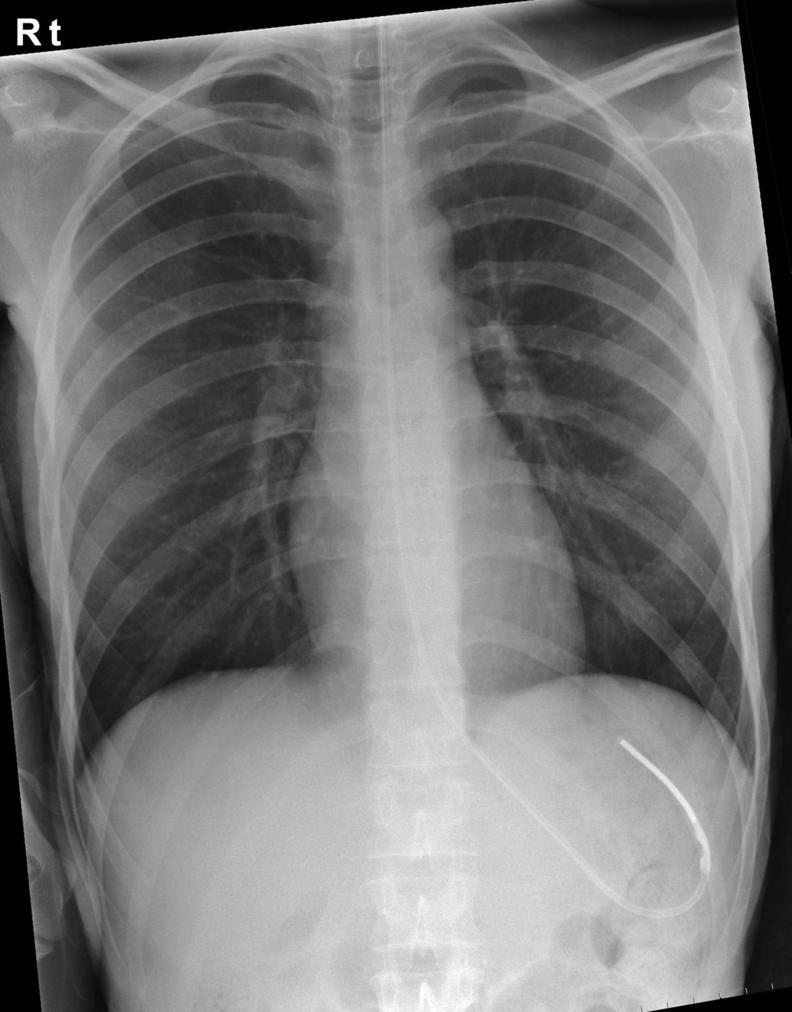

15) Organise chest x-ray to ensure NGT is in correct position.

The correct position is that you can visualise the NGT passing midline through the thorax, past the carina, and ending under the left hemi-diaphragm in the general region of the stomach.